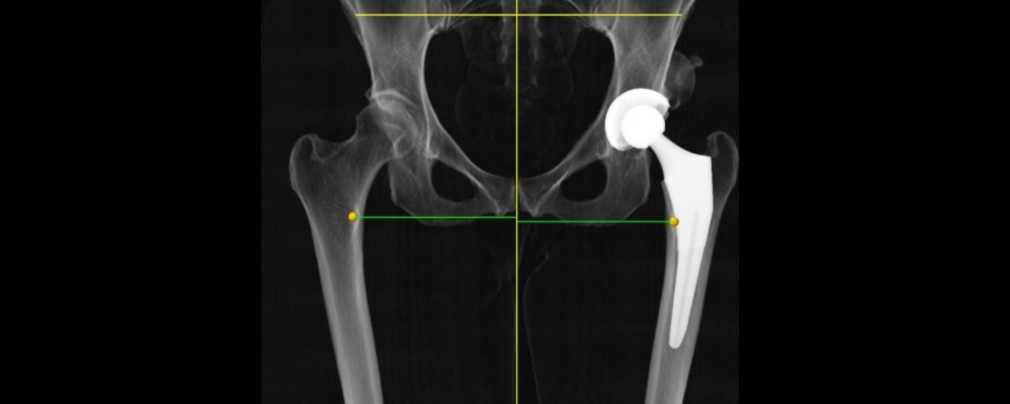

Αποκατάσταση Κατάγματος ισχίου με το Ρομποτικό σύστημα ΜΑΚΟ